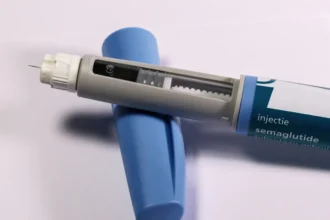

Caneta brasileira contra diabetes avança e acirra corrida com Ozempic; veja

O mercado brasileiro de medicamentos à base de…